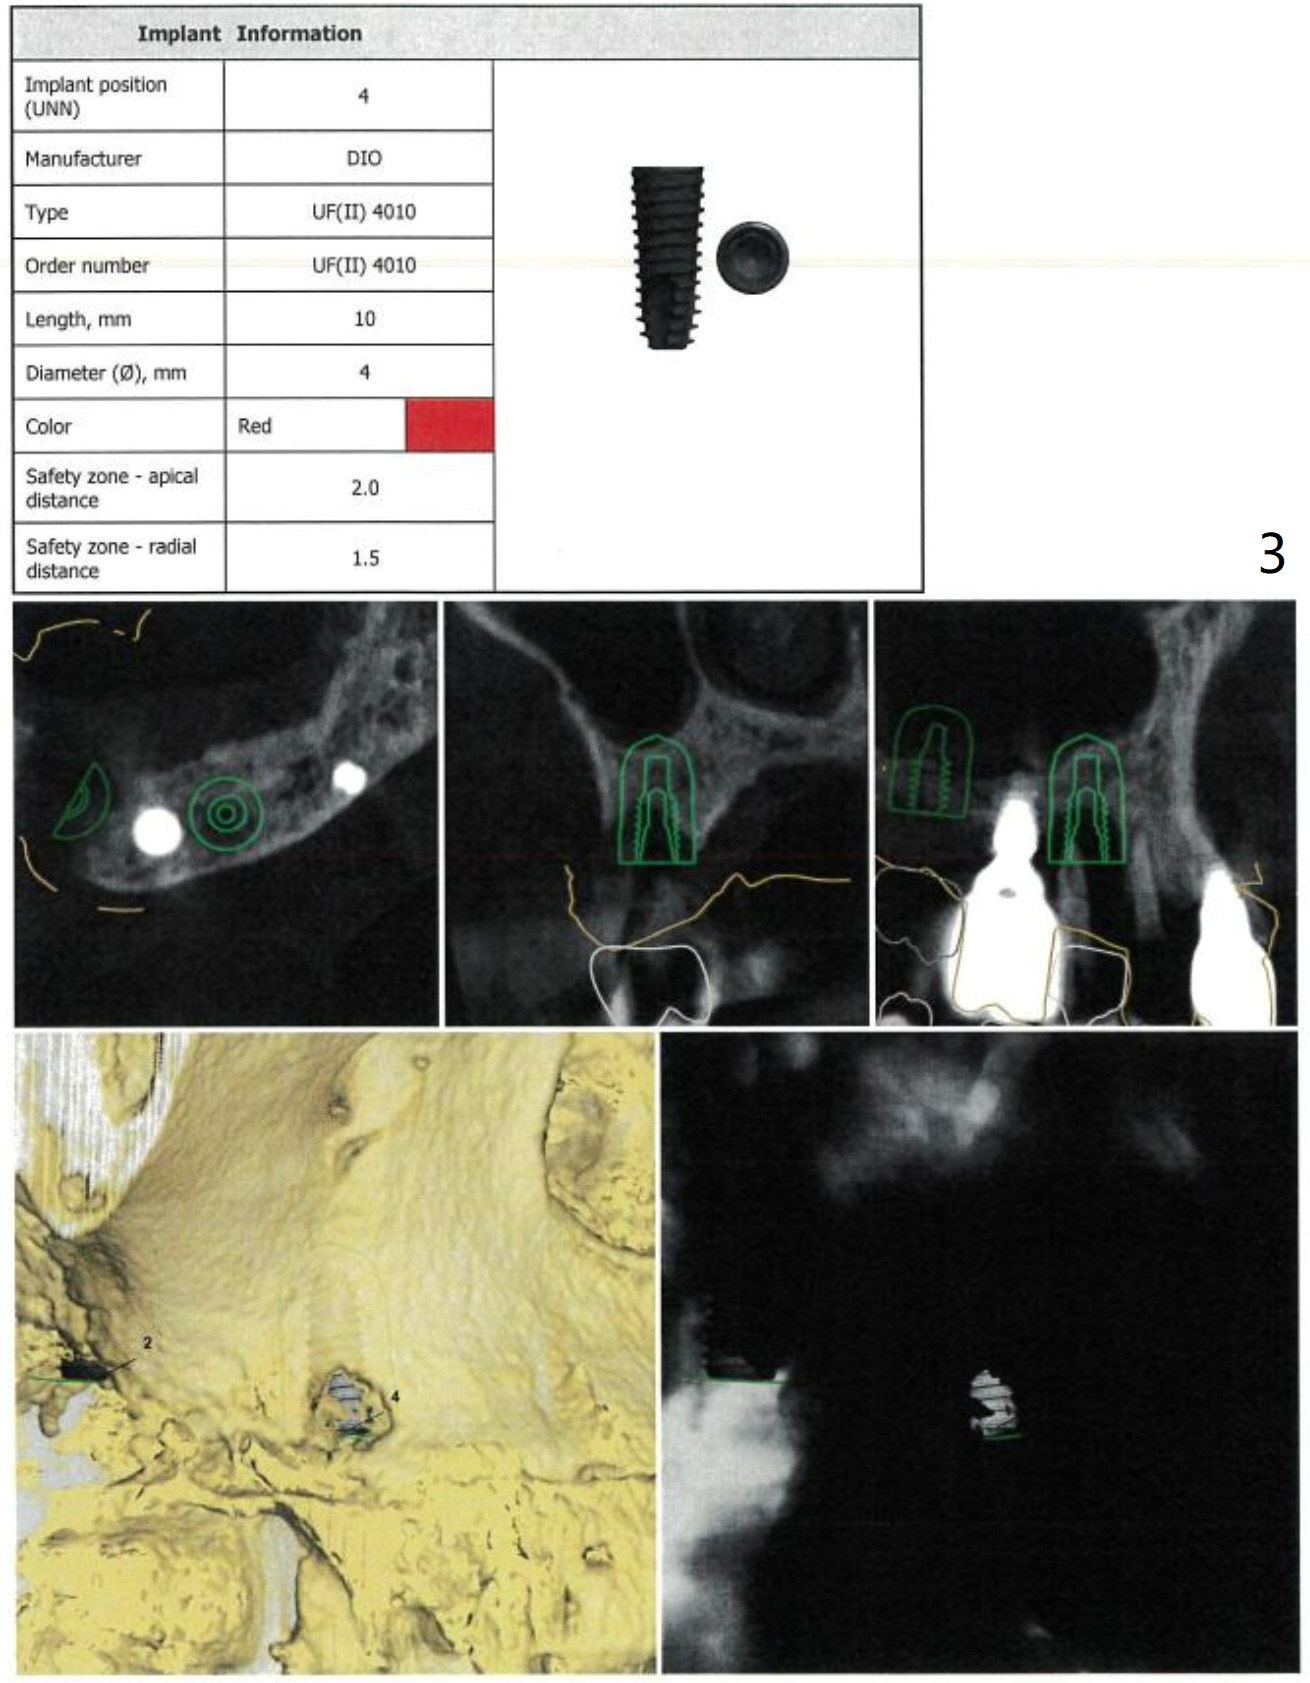

Two Implants

In fact the patient agrees to have 2 implants (#2 and 4) to be placed at the same time.